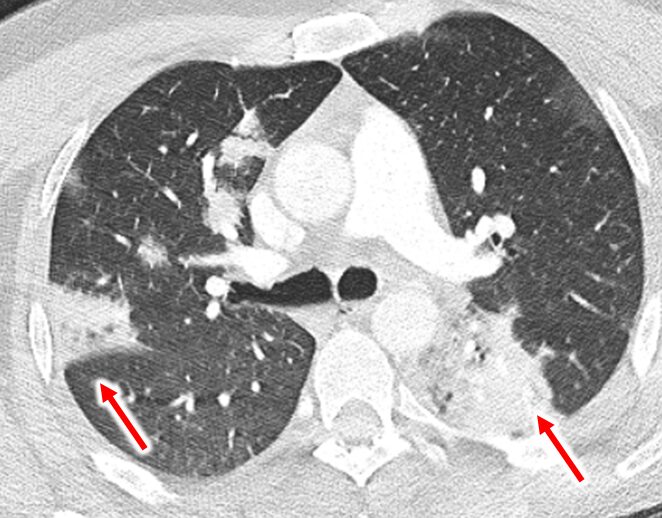

胸部CTは“足側から見上げるビュー”で撮影されているため、画像の左側=患者の右肺、右側=左肺に相当します。

左右の赤い矢印の部位には白い陰影が認められ、肺炎に特徴的な浸潤影と判断できます。